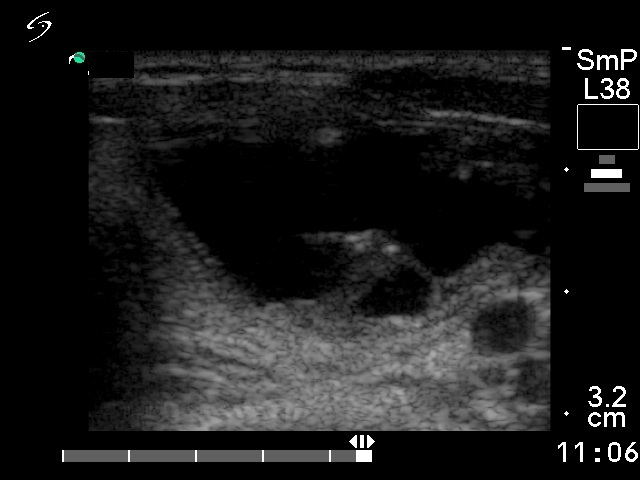

Various hyperechogenic granules are

within the nodule.

The dorsal solid part was unchanged

after evacuation of the cyst. It is also suspicious because of the

hyperechogenic granules.